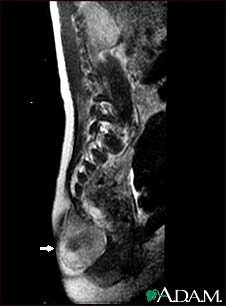

Teratoma - MRI scan

This MRI scan shows a tumor (teratoma) at the base of the spine (seen on the left lower edge of the screen), located in the sacrum and coccyx (sacrococcygeal) area. Teratomas are present at birth and may contain hair, teeth, and other tissues.